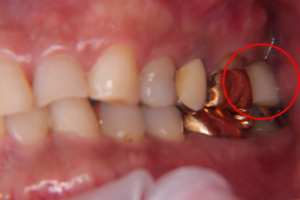

①虫歯の為抜歯が必要であった歯(右上の前から4番目の歯)の抜歯を行い(上の写真)

②そして、抜いた箇所にそのままインプラントを埋入(抜歯即時インプラント)

③インプラントを埋入後、仮歯を装着して終了です。

こちらがインプラント治療を終えた歯です。